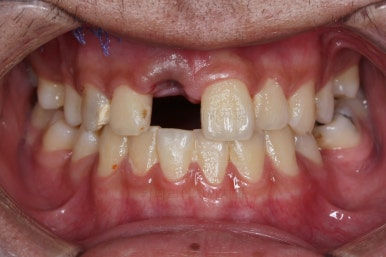

초진 때의 사진입니다.

전반적으로 치열이 삐뚤하고 불균일한 양상이긴 하지만 꼭 이런 부분들까지 교정해야 하는 건 아니에요.

치열에 대한 본인의 개선 의사가 있다면 전반적인 교정을 해줄 필요가 있지만, 그렇지 않다면 굳이 할 필요가 없는거죠.